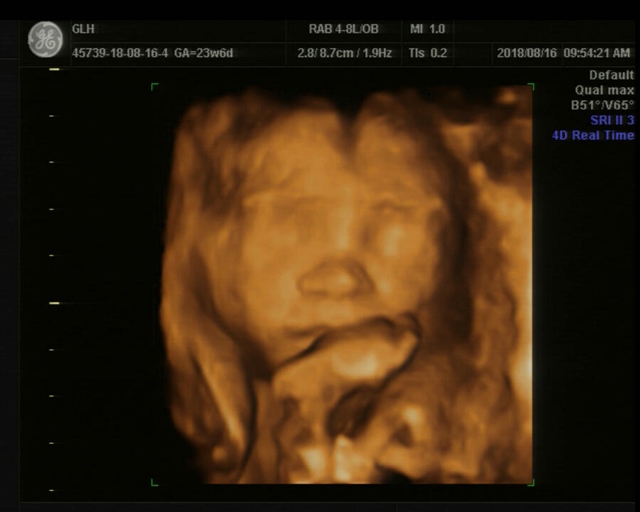

sunshine

孕10周+2天

好可爱 还撅嘴